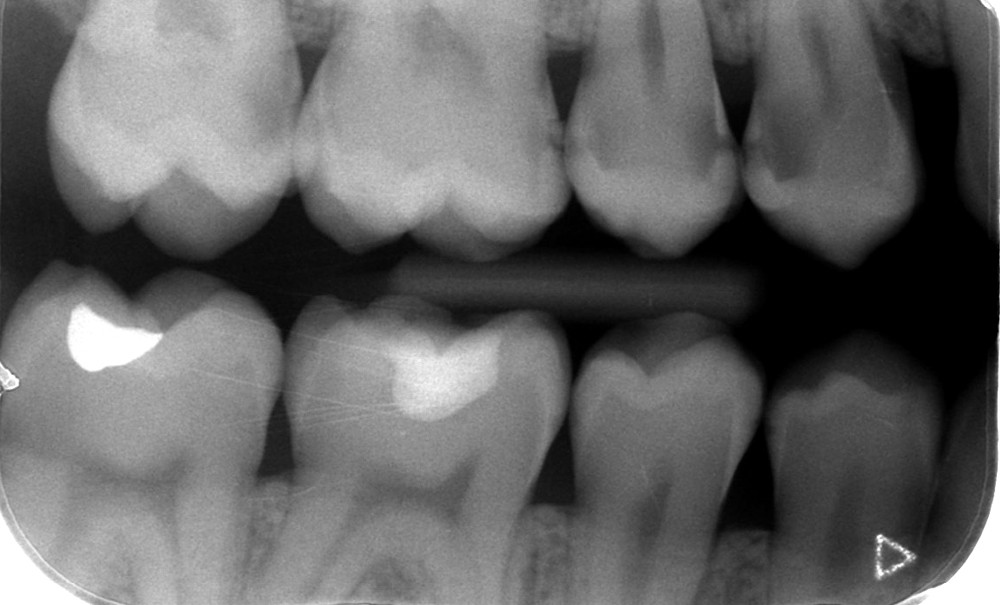

Gestion du processus carieux : les dernières recommandations issues de consensus internationaux

De nombreuses enquêtes de pratique ont montré la variation des décisions diagnostiques et thérapeutiques en cariologie d’un pays à l’autre mais aussi entre les praticiens d’un même pays [4, 5]. Dans ce contexte, la nécessité de recommandations applicables en pratique clinique se fait ressentir. Aussi, en 2018, trois associations scientifiques – l’European Organisation for Caries Research (ORCA), l’European Federation of Conservative Dentistry (EFCD) et la Deutsche Gesellschaft für Zahnerhaltung (DGZ) – ayant des intérêts communs pour la cariologie et la dentisterie conservative se sont associées (consensus et processus-e-Delphi) (encadré ci-dessous) dans le but de définir des recommandations à propos de la gestion de la MC. Trois thèmes ont ainsi été développés – la MC chez l’enfant/adolescent, l’adulte et la personne âgée – et trois articles publiés [6-8].

L’objectif du présent article est, après avoir exposé les spécificités du processus carieux et de la MC successivement chez l’enfant/adolescent, l’adulte puis la personne âgée, de synthétiser, en français, les recommandations ORCA-EFCD-DGZ édictées à propos de la gestion de la MC pour ces trois tranches d’âge (tableaux 1-3) [6-8].